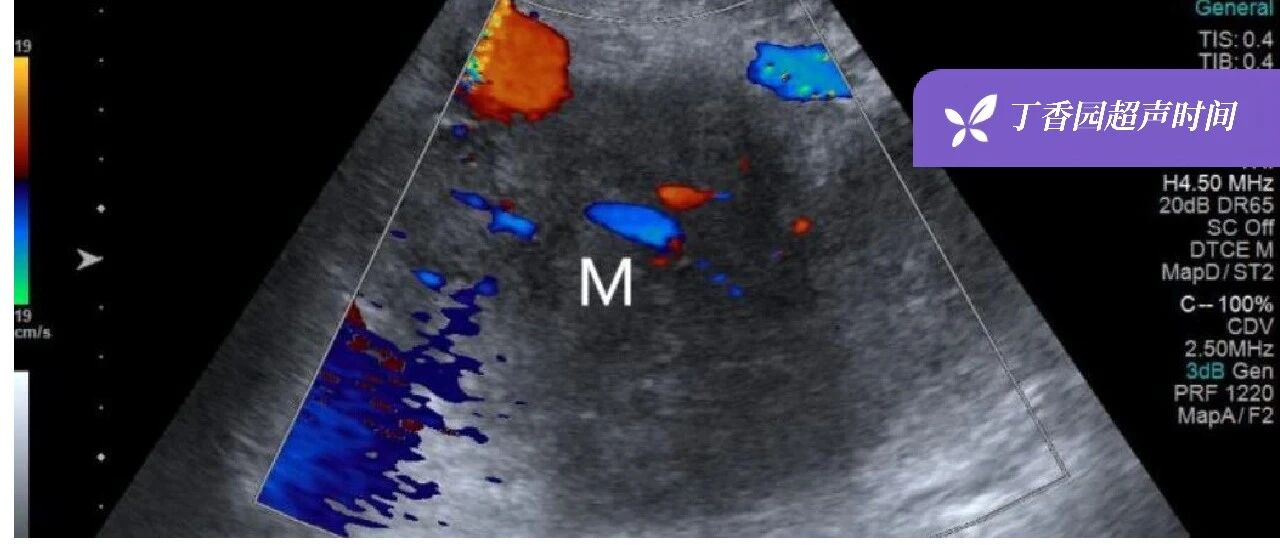

右乳巨大肿物持续生长 27 年,内科、外科、放疗科,谁先来治疗